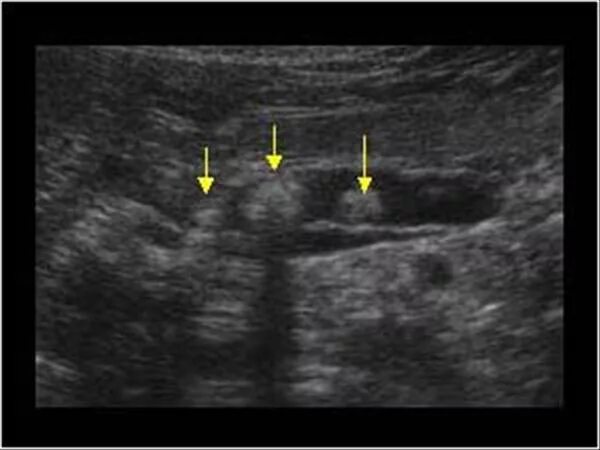

Расширен проток